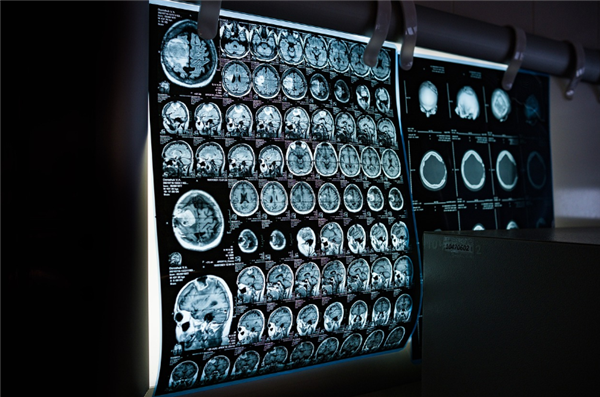

4月21日消息,据报道,美国加州大学旧金山分校(UCSF)最新研究发现,CT扫描导致的辐射暴露每年可能引发约10.3万例癌症,占全美癌症病例的5%。

CT在肿瘤检测和疾病诊断中具有不可替代的广泛用途。自2007年以来,美国年度CT检查量激增30%。但CT会使患者暴露于致癌的电离辐射中。

研究人员分析了来自6150万名患者的9300万次CT检查。扫描次数随年龄增长而增加,在60至69岁成年人中达到峰值。儿童占扫描总量的4.2%。研究人员排除了患者生命最后一年进行的检查,因为这些检查不太可能引发癌症。